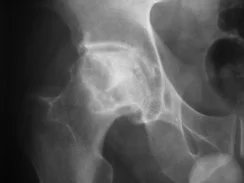

因此有长期大量喝酒习惯的朋友们需要警惕,一旦出现上述情况,应及时到正规医院就诊。通过X片和核磁共振可以明确诊断,核磁对于早期病变有着非常好的敏感性,从而可以帮助患者及早治疗,避免病情进一步严重。

在酒精性股骨头坏死的早期,可以通过戒酒、扶双拐减轻负重、口服促进微循环及骨坏死修复的相关药物来减慢股骨头坏死的进展;并且可以根据早期股骨头外形尚完整,单纯内部出现囊性改变及硬化修复的特点,采用股骨头髓心减压结合植骨的方式,将股骨头内缺血坏死的区域打通,重新建立血供,并给予足够强度的骨质支撑 ,从而期望通过人体的自我修复来达到痊愈的目的,据我们关节中心的经验,早期的股骨头坏死通过这种办法, 70%~80%左右患者可以获得满意效果,从而保住自己的股骨头。

但如果X线上发现股骨头外形已经改变,出现了塌陷,这种情况属于股骨头坏死的晚期,保守治疗的效果往往不令人满意,解决问题的根本是通过关节置换的方式来获得一个人工的关节。